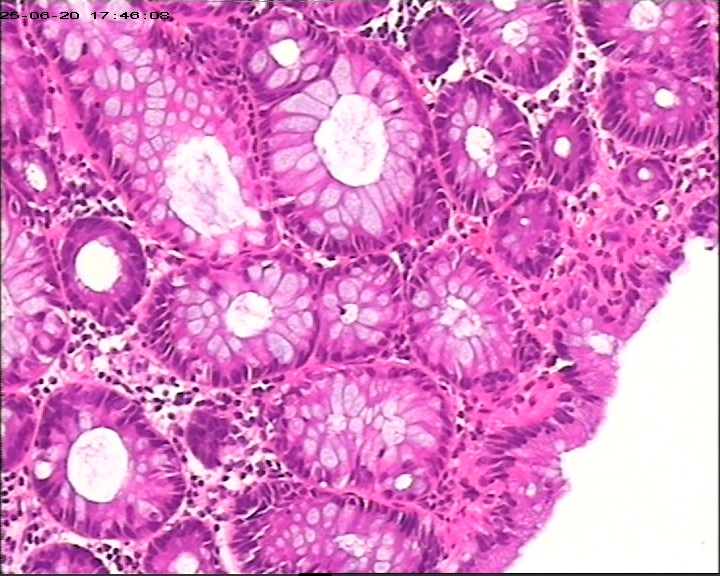

直肠息肉组织,请帮忙看看,谢谢

性别

男

年龄

66岁

临床诊断

一般病史

腹痛1周加重伴黑便3天

标本名称

直肠息肉

灰白组织1块,直径0.6cm。

增生性息肉